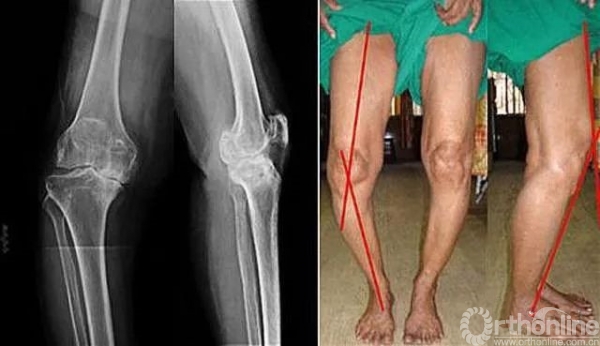

图9 老化的膝关节,左图为X线表现,骨缝已快看不到了,表明膝关节的软骨磨没了;右图可见典型的改变,一是膝关节外撇,二是膝关节伸不直